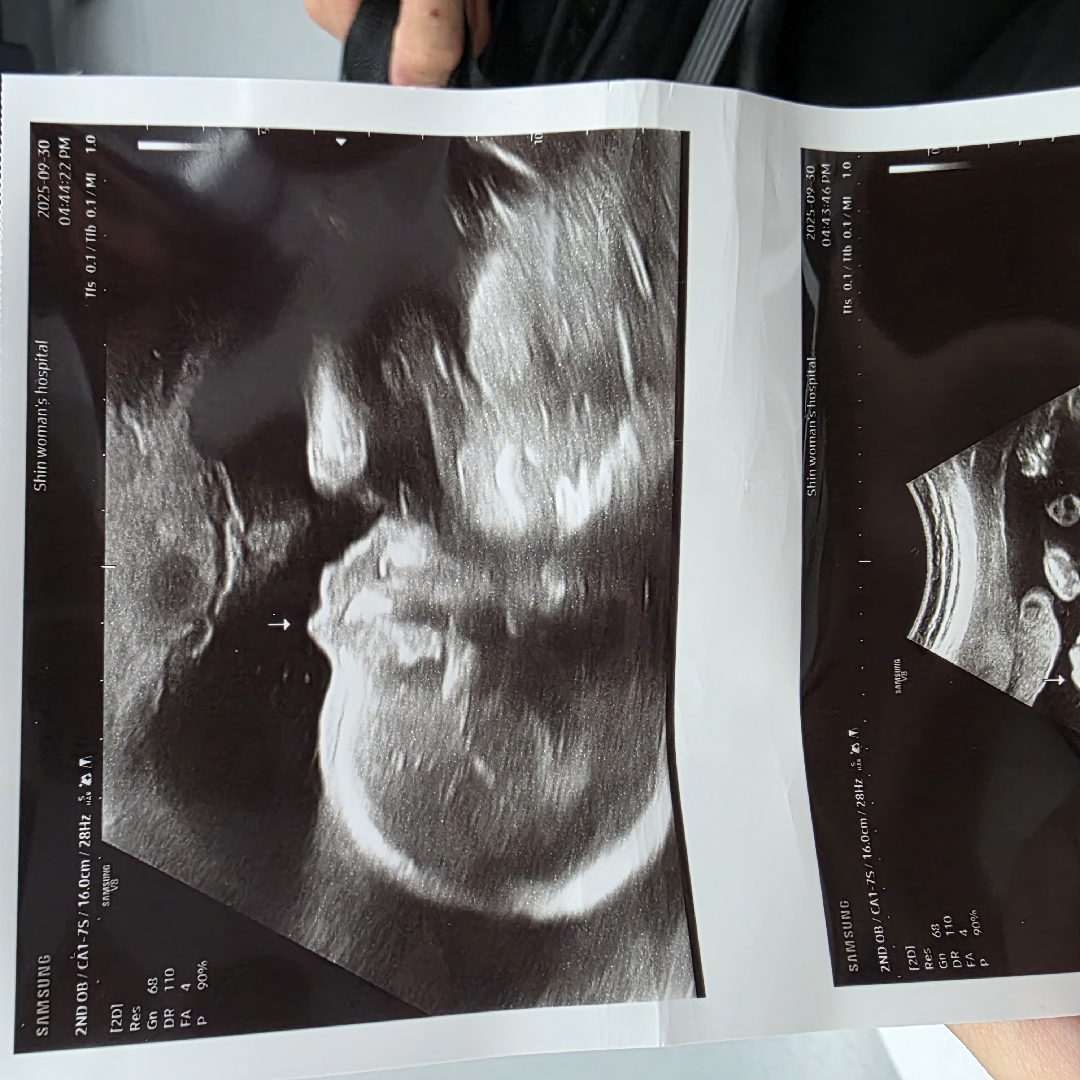

22주차 아들입니다 이정도면 콧대 높은건지 낮은건지 알수있나요 ?! *아빠는 코가 높고, 엄마는 코가 낮아요 🤣